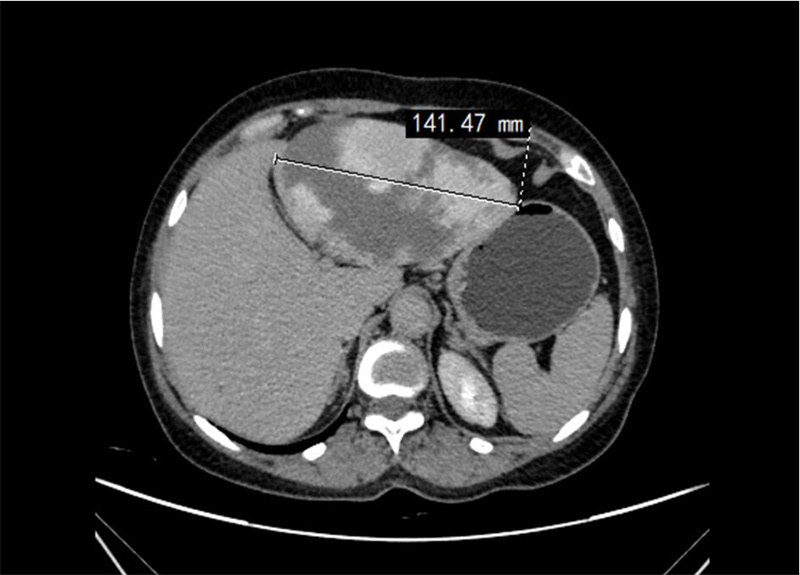

術(shù)前腹部CT照片

今年50多歲的任女士近期突感腹脹。起初,她并未將腹脹放在心上,以為只是普通的腸胃不適。但隨著時(shí)間的推移,任女士少量進(jìn)食就會導(dǎo)致嚴(yán)重腹脹,而且在肚子上還能摸到隆起的包塊,遂趕緊到十堰人醫(yī)肝膽胰腺外科門診就診。然而,初步的檢查結(jié)果卻讓在場的所有人大吃一驚:她的肝臟上竟然長出了一個(gè)直徑約14厘米的巨大腫瘤!面對這突如其來的結(jié)果,任女士及其家人陷入焦慮。因情況危急,接診醫(yī)生將其收入院接受治療。

入院后,經(jīng)過進(jìn)一步的詳細(xì)檢查發(fā)現(xiàn),任女士肝臟上的腫瘤為肝血管瘤,體積巨大,壓迫了周圍的消化道,這是導(dǎo)致任女士持續(xù)腹脹癥狀的主要原因,但好在這是個(gè)良性腫瘤。不過由于任女士的血管瘤體積龐大,一旦破裂,后果將不堪設(shè)想,可能引發(fā)大出血等嚴(yán)重后果,甚至危及生命,需緊急手術(shù)治療。